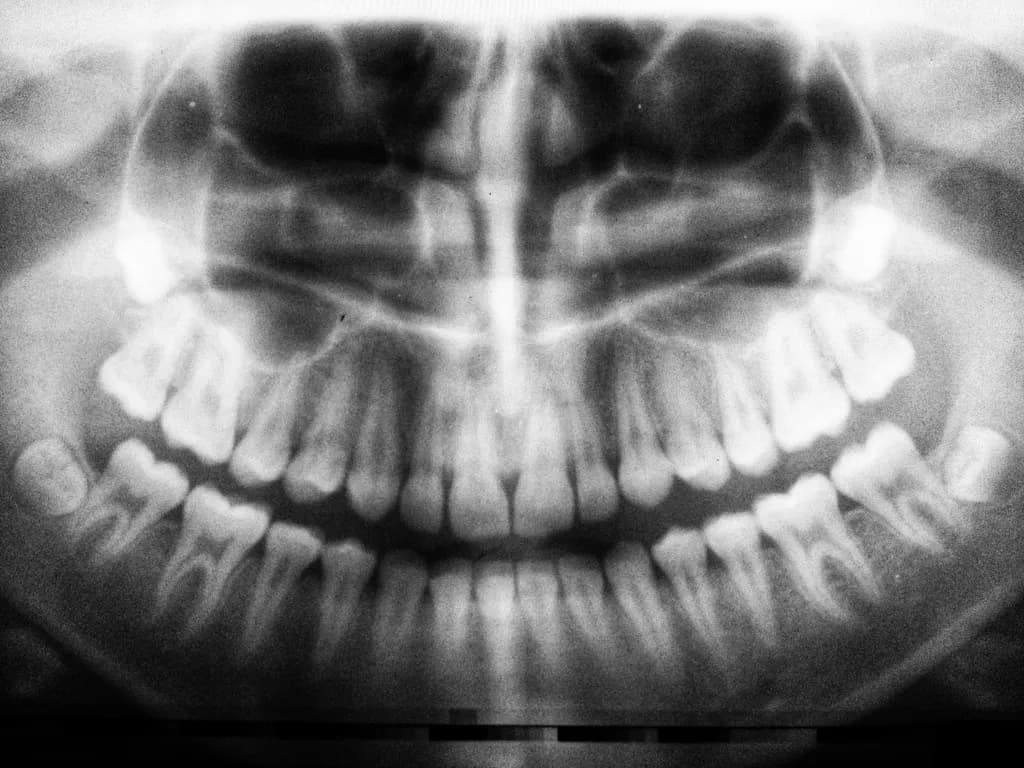

Najczęściej stosowane są RTG punktowe, które obejmuje pojedynczy ząb wraz z jego korzeniami i najbliższym otoczeniem – to badanie jest niezbędne przy leczeniu kanałowym lub ocenie zmian zapalnych. RTG skrzydłowo-zgryzowe pozwala zobrazować korony kilku sąsiadujących zębów, co ułatwia wykrycie próchnicy międzyzębowej. Pantomogram, czyli zdjęcie panoramiczne, przedstawia oba łuki zębowe oraz kości szczęki i żuchwy – jest podstawą do planowania leczenia ortodontycznego, protetycznego czy chirurgicznego. W przypadku konieczności dokładnej analizy profilu twarzoczaszki wykonuje się RTG cefalometryczne, szczególnie przydatne w ortodoncji. Najbardziej zaawansowaną formą diagnostyki jest tomografia komputerowa 3D (CBCT), która umożliwia trójwymiarową ocenę wszystkich struktur jamy ustnej i twarzoczaszki – to rozwiązanie stosowane m.in. przed zabiegami implantologicznymi lub w skomplikowanych przypadkach chirurgicznych.

Samo wykonanie zdjęcia RTG trwa zazwyczaj od kilkunastu do kilkudziesięciu sekund i jest całkowicie bezbolesne. W przypadku badań wewnątrzustnych (np. punktowych lub skrzydłowo-zgryzowych) do jamy ustnej wprowadza się niewielki detektor lub kliszę, którą pacjent przytrzymuje za wskazanym zębem. Natomiast badania zewnątrzustne, takie jak pantomogram czy cefalometria, polegają na ustawieniu głowy w odpowiedniej pozycji – urządzenie automatycznie wykonuje zdjęcie całej szczęki lub czaszki bez konieczności wkładania czegokolwiek do ust. Po zakończeniu procedury wynik badania jest dostępny niemal natychmiast – w formie cyfrowej lub wydruku, co pozwala lekarzowi na szybkie omówienie dalszych kroków diagnostycznych lub terapeutycznych.